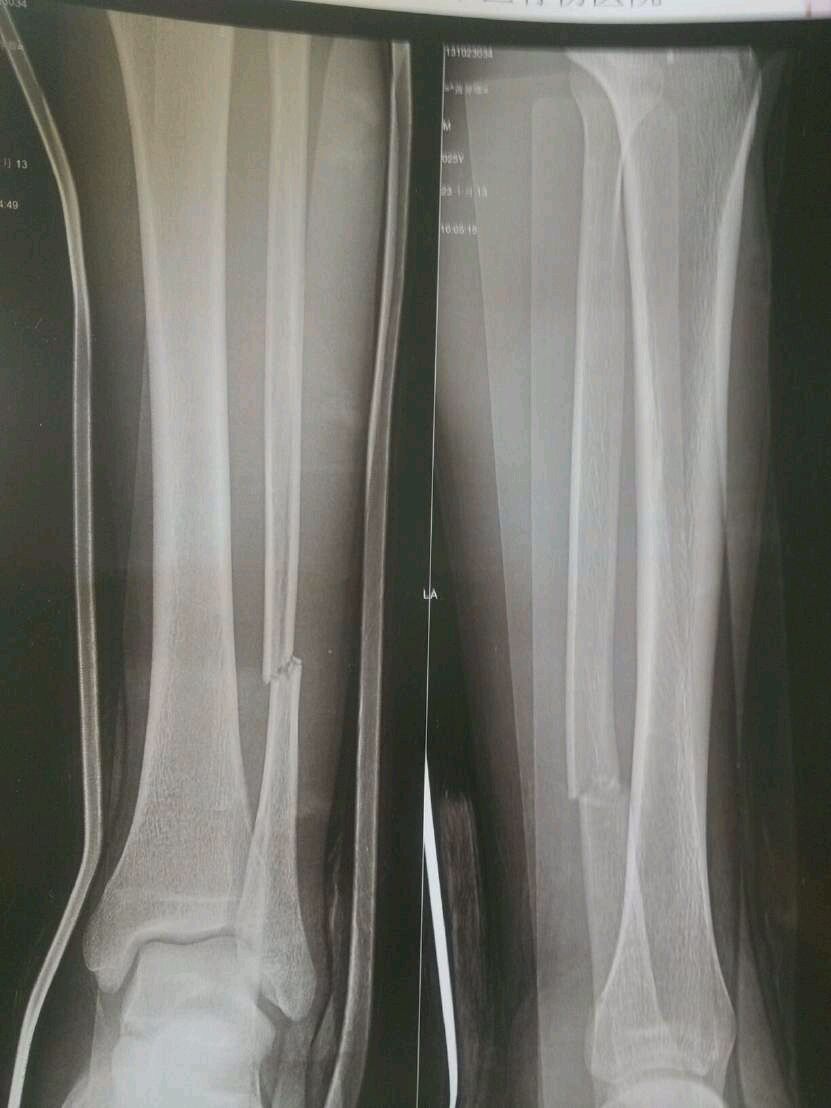

帮忙看看必须手术吗

腓骨骨折、建议复位、可保守治疗

如果只有腓骨的话,没有必要。

我的腓骨没有理,让他自己长好。

可以保守治疗

完全可以保守治疗,前提是必须找一个中医手法复位再安夹板!

完全没必要手术